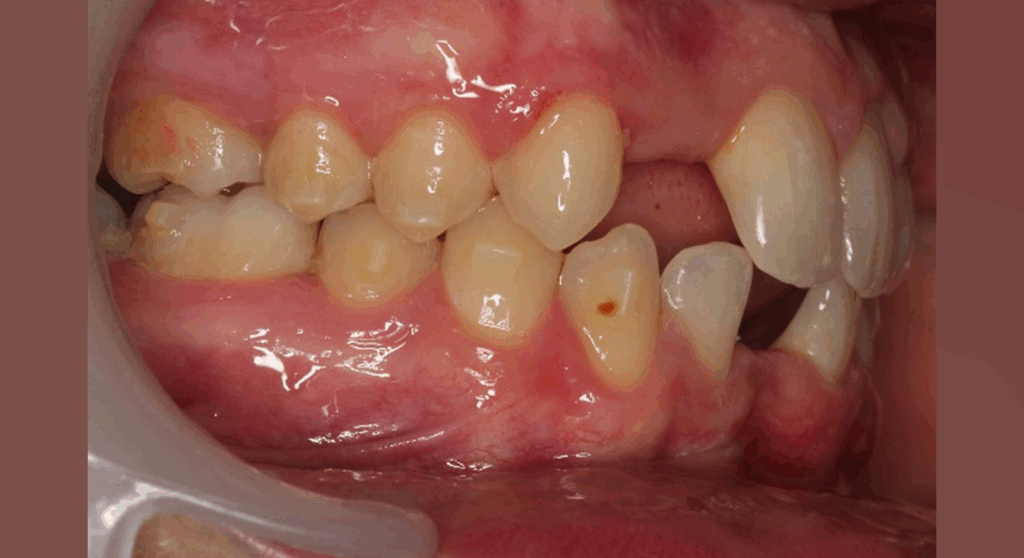

Skeletal Class II due to mandibular retrognathia, proclination of maxillary incisors, narrow arch creating a V-shaped arch, agenesis of 12, 31, 41, hyperdivergent facial pattern, moderate deep bite (2 mm), increased overjet (9 mm), asymmetric canine and molar Class II due to mandibular deviation to the left, maxillary midline deviation related to agenesis of 12, distal rotation of 35 and 45, and pronounced lower curve of Spee.

Labial incompetence, mouth breathing, tongue dysfunction

Stimulate mandibular growth, reduce overjet, correct Class II relationships, level the curve of Spee, manage space opening for agenesis of 12, 31, and 41, recenter midlines, improve oral function.